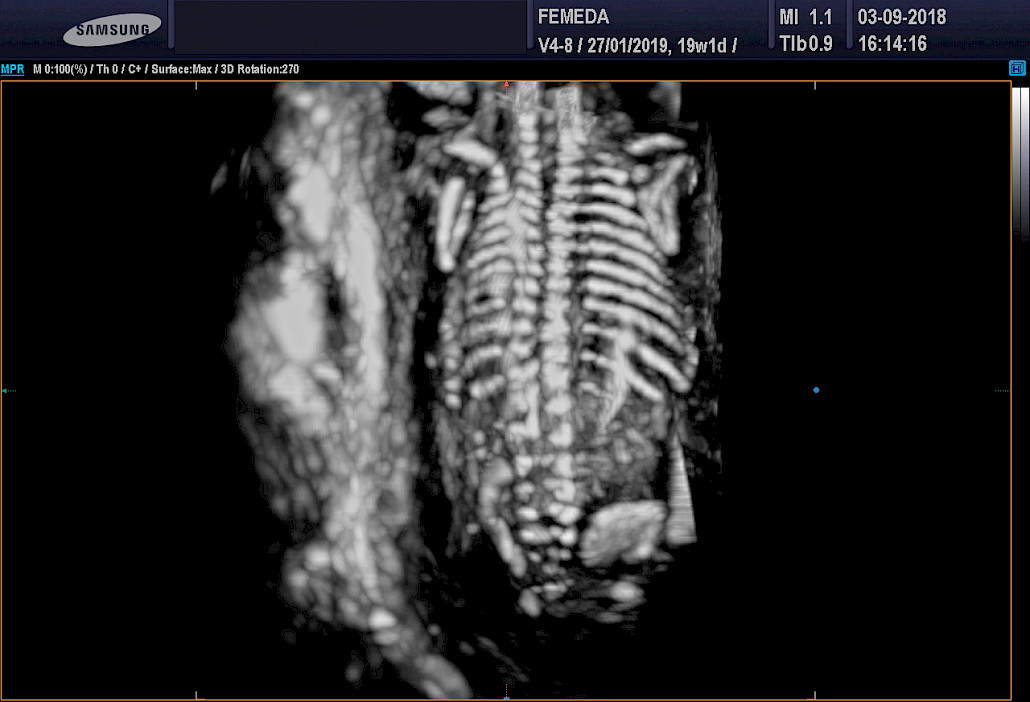

3D ja 4D-tekniikat soveltuvat erityisen hyvin sikiön kasvojen anatomian tutkimiseen. Tutkimuksessa poissuljetaan mahdollinen huulihalkio ja kasvojen profiilissa esiintyvät muut poikkeamat, kuten liian pieni leuka. Samalla selvitetään korvien anatomia ja niiden sijainti. Tekniikan avulla selvitetään raajojen asennot, sekä sormien ja varpaiden lukumäärä ja niiden liikkuvuus. Lisäksi tutkitaan koko selkärangan rakenne ja suljetaan pois poikkeamat, kuten puuttuvat lapa- tai olkaluut.

Mikä on paras ajankohta 4D-ultraäänitutkimukselle?

4D-tutkimukset voidaan tehdään koska tahansa raskauden aikana. Sikiön rakenne voidaan selvittää kuitenkin parhaiten raskausviikoilla 19-30. Sikiön kasvonpiirteet näkyvät parhaiten raskausviikoilla 22-28. Niukka lapsiveden määrä, epäedullinen sikiön asento, äidin ylipaino tai paksut vatsanpeitteet saattavat vaikuttaa 4D-kuvien laatuun, mutta ne harvoin estävät tyydyttävän arvion saamista sikiön anatomiasta.